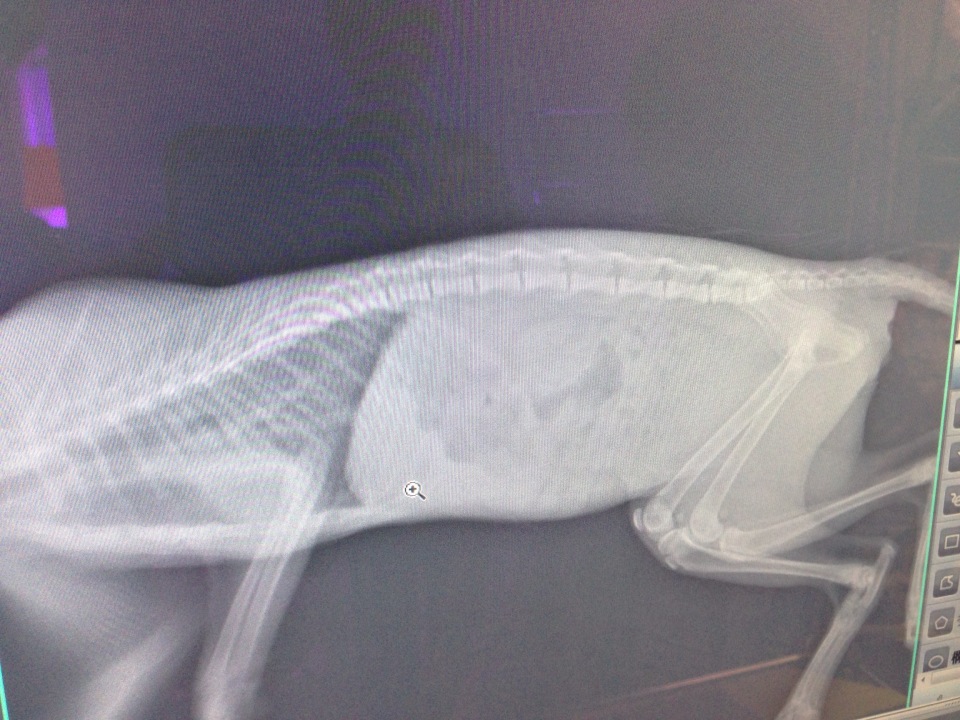

主題: 腹瀉嚴重脫肛的小虎斑 申請者姓名: 臺北市支持流浪貓絕育計劃協會 花色: 申請日期: 2013-07-15 18:11:07 申請者部落格: 申請者臉書網址: 所在縣市/合作醫院: 台北市/極光動物醫院 治療費用: 5080元 需求人數: 12人 已結案 (2013-09-03 16:26:47) 報名人員: Ani Chang(已付款)、Huimin Liu(已付款)、夙夙 x2(已付款)、林慧美(已付款)、beforn(已付款)、李脆脆 x2(已付款)、貝貝(已付款)、Bobo(已付款)、鄭蘊芬(已付款)、Chenyu Chang(已付款)、 候補人員: 彭小豬、 動物病情說明: 民眾求助有小貓咪腹瀉嚴重屁股後面紅紅的一截疑似脫肛脫肛,捕捉送醫治療,第一階段手術縫合固定了三次,一直沒有辦法得到改善,第二階段轉院後醫師將縫線拆掉,將直腸彎曲的部分作調整,將脫肛部位推回,之後給予罐頭和軟便寄,觀察至今已經七天尚未復發,希望貓咪可以就此擺脫病苦。

(照片4、5是脫肛縫合手術的線,後來已經拆掉)